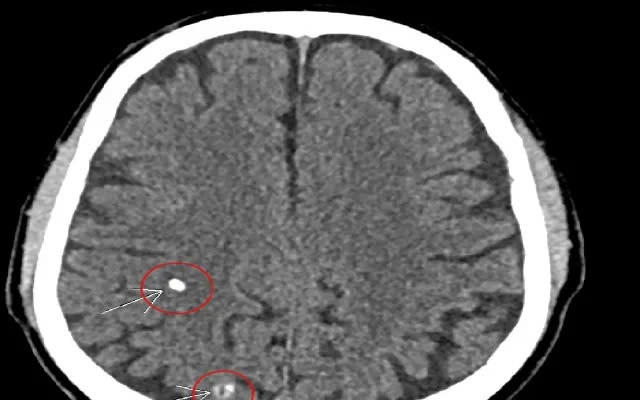

Nhu mô não có hình ảnh rải rác các di chứng ấu trùng sán não, và kèm theo tổn thương viêm đa xoang, xơ vữa vôi hoá động mạch cảnh hai bên đoạn xoang hang.

![]() |

| Đi khám bệnh tuyến giáp, người đàn ông 66 tuổi bất ngờ phát hiện sán não |